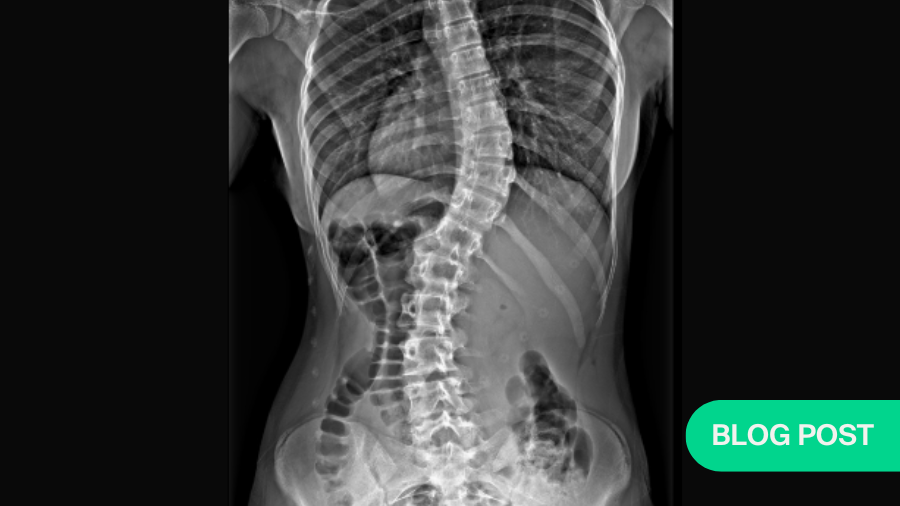

AO Spine@AOSpine·

#Scoliosis exercises are widely used in Adolescent Idiopathic Scoliosis but their efficacy in reducing curve progression has been debatable. With new research evidence on the Schroth Method, Dr Emre Acaroğlu remains skeptical. What do you think? 🔗 brnw.ch/21wKUM6

Schroth egzersizleri uzun süredir skolyoz hastalarının zihinlerini bulandıran bir konu. Herhangi bir yararı var mı? Yeni yayınlanan bir meta analiz bu soruya ışık tutuyor ve hiçbir gerçek yararı olmadığını söylüyor. Blog'umda daha fazla ayrıntı mevcut: omurgadoktoru.blogspot.com/2024/05/schrot…